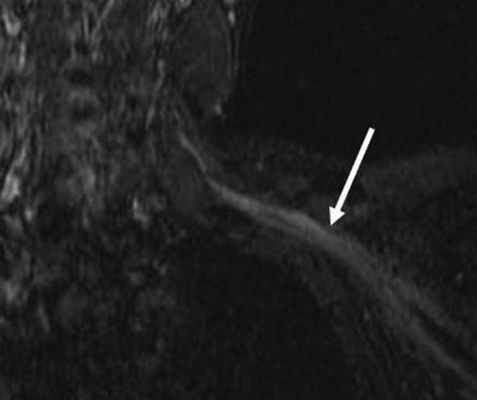

МРТ мягких тканей шеи. Т2-взвешенная корональная томограмма. Повреждение ствола плечевого сплетения.

Повреждения дистальнее корешка видны при МРТ мягких тканей шеи. Повреждение ствола видно как его разрыв и гиперинтенсивность на Т2-взвешенных МРТ.